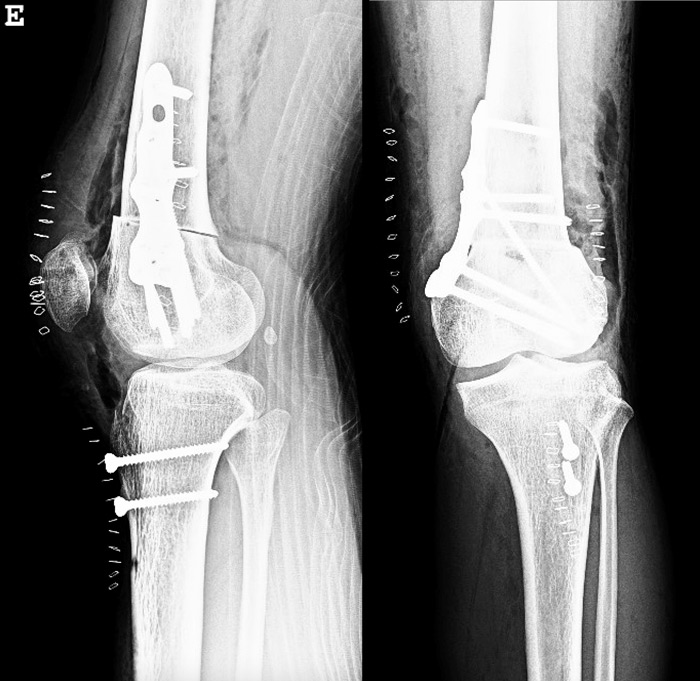

Post-operative X-rays

Post-op X-Rays